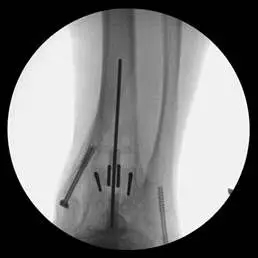

These first three pics are placement of screws in the medial malleolus and distal fibula to aid in stability.